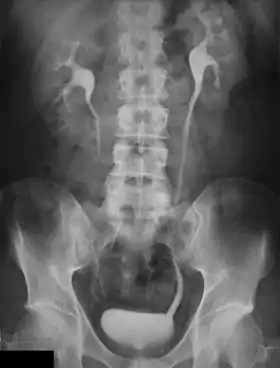

پیلوگرام داخل وریدی، (به انگلیسی: (Intravenous pyelogram (IVP) یک روش تصویربرداری است که در آن ابتدا ماده حاجب (مادهای که در عکسهایی که با اشعه – X برداشته میشود قابل رؤیت است) را در یکی از وریدهای بیمار تزریق مینمایند. ماده حاجب هنگام عبور جریان خون از کلیه تصفیه شده به داخل ادرار ترشح میشود، سپس در فواصل زمانی منظم (مثلاً ده دقیقه) با استفاده از اشعه – X از کلیه، حالب و مثانه عکسبرداری میکنند. هنگامیکه ماده حاجب در سیستم دفع ادراری حرکت میکند، شکل کلی کلیهها، حالب، و مثانه را ترسیم میکند و نهایتاً در مثانه تجمع مییابد و دفع ادراری میشود. اروگرافی داخل وریدی ممکن است برای بررسی اولیه بسیاری از مشکلات ارولوژیک مشکوک،به ویژه ضایعات کلیوی و حالب استفاده گردد.همچنین از آن میتوان جهت تخمین کلی عملکرد کلیه استفاده کرد .پس از تزریق ماده حاجب(سدیم دیاتریزوات یا مگلومین دیاتریزوات) چندین تصویر متوالی گرفته میشود تا ساختارهای تخلیه شونده قسمتهای فوقانی و تحتانی دستگاه ادراری را مشاهده نمایند.

از IVP معمولاً برای یافتن انسداد در جریان ادرار، بررسی عملکرد کلیهها و علل هماچوری استفاده میکنند.